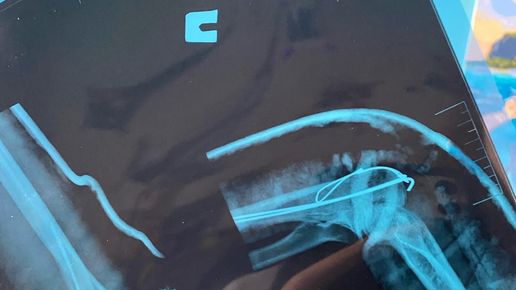

История о том, как я сломала локоть (или перелом локтевого отростка со смещением)

Перелом локтя. Часть очередная.

В прошлый раз мы остановились на том, что вынеся мозг травматологам я добилась свободы в лучезапястном суставе. Сегодня объясню для чего это делалось. Дисклеймер! Не повторять самостоятельно! Только если у вас есть хорошие врачи в лице травматолога и реабилитолога! Самостоятельно невозможно правильно себя оценить. Поверьте врачу, который носит свой перелом к другим врачам и сама даже не пытается что-то делать без их назначений. Вернёмся к тому, что при переломе локтя требуется полностью выключить...